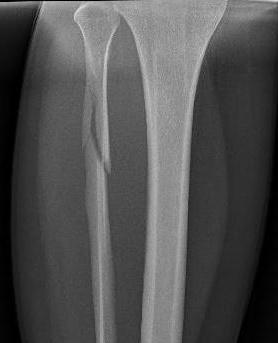

Xray

Maisonneuve injury with proximal fibular fracture and increased medial clear space